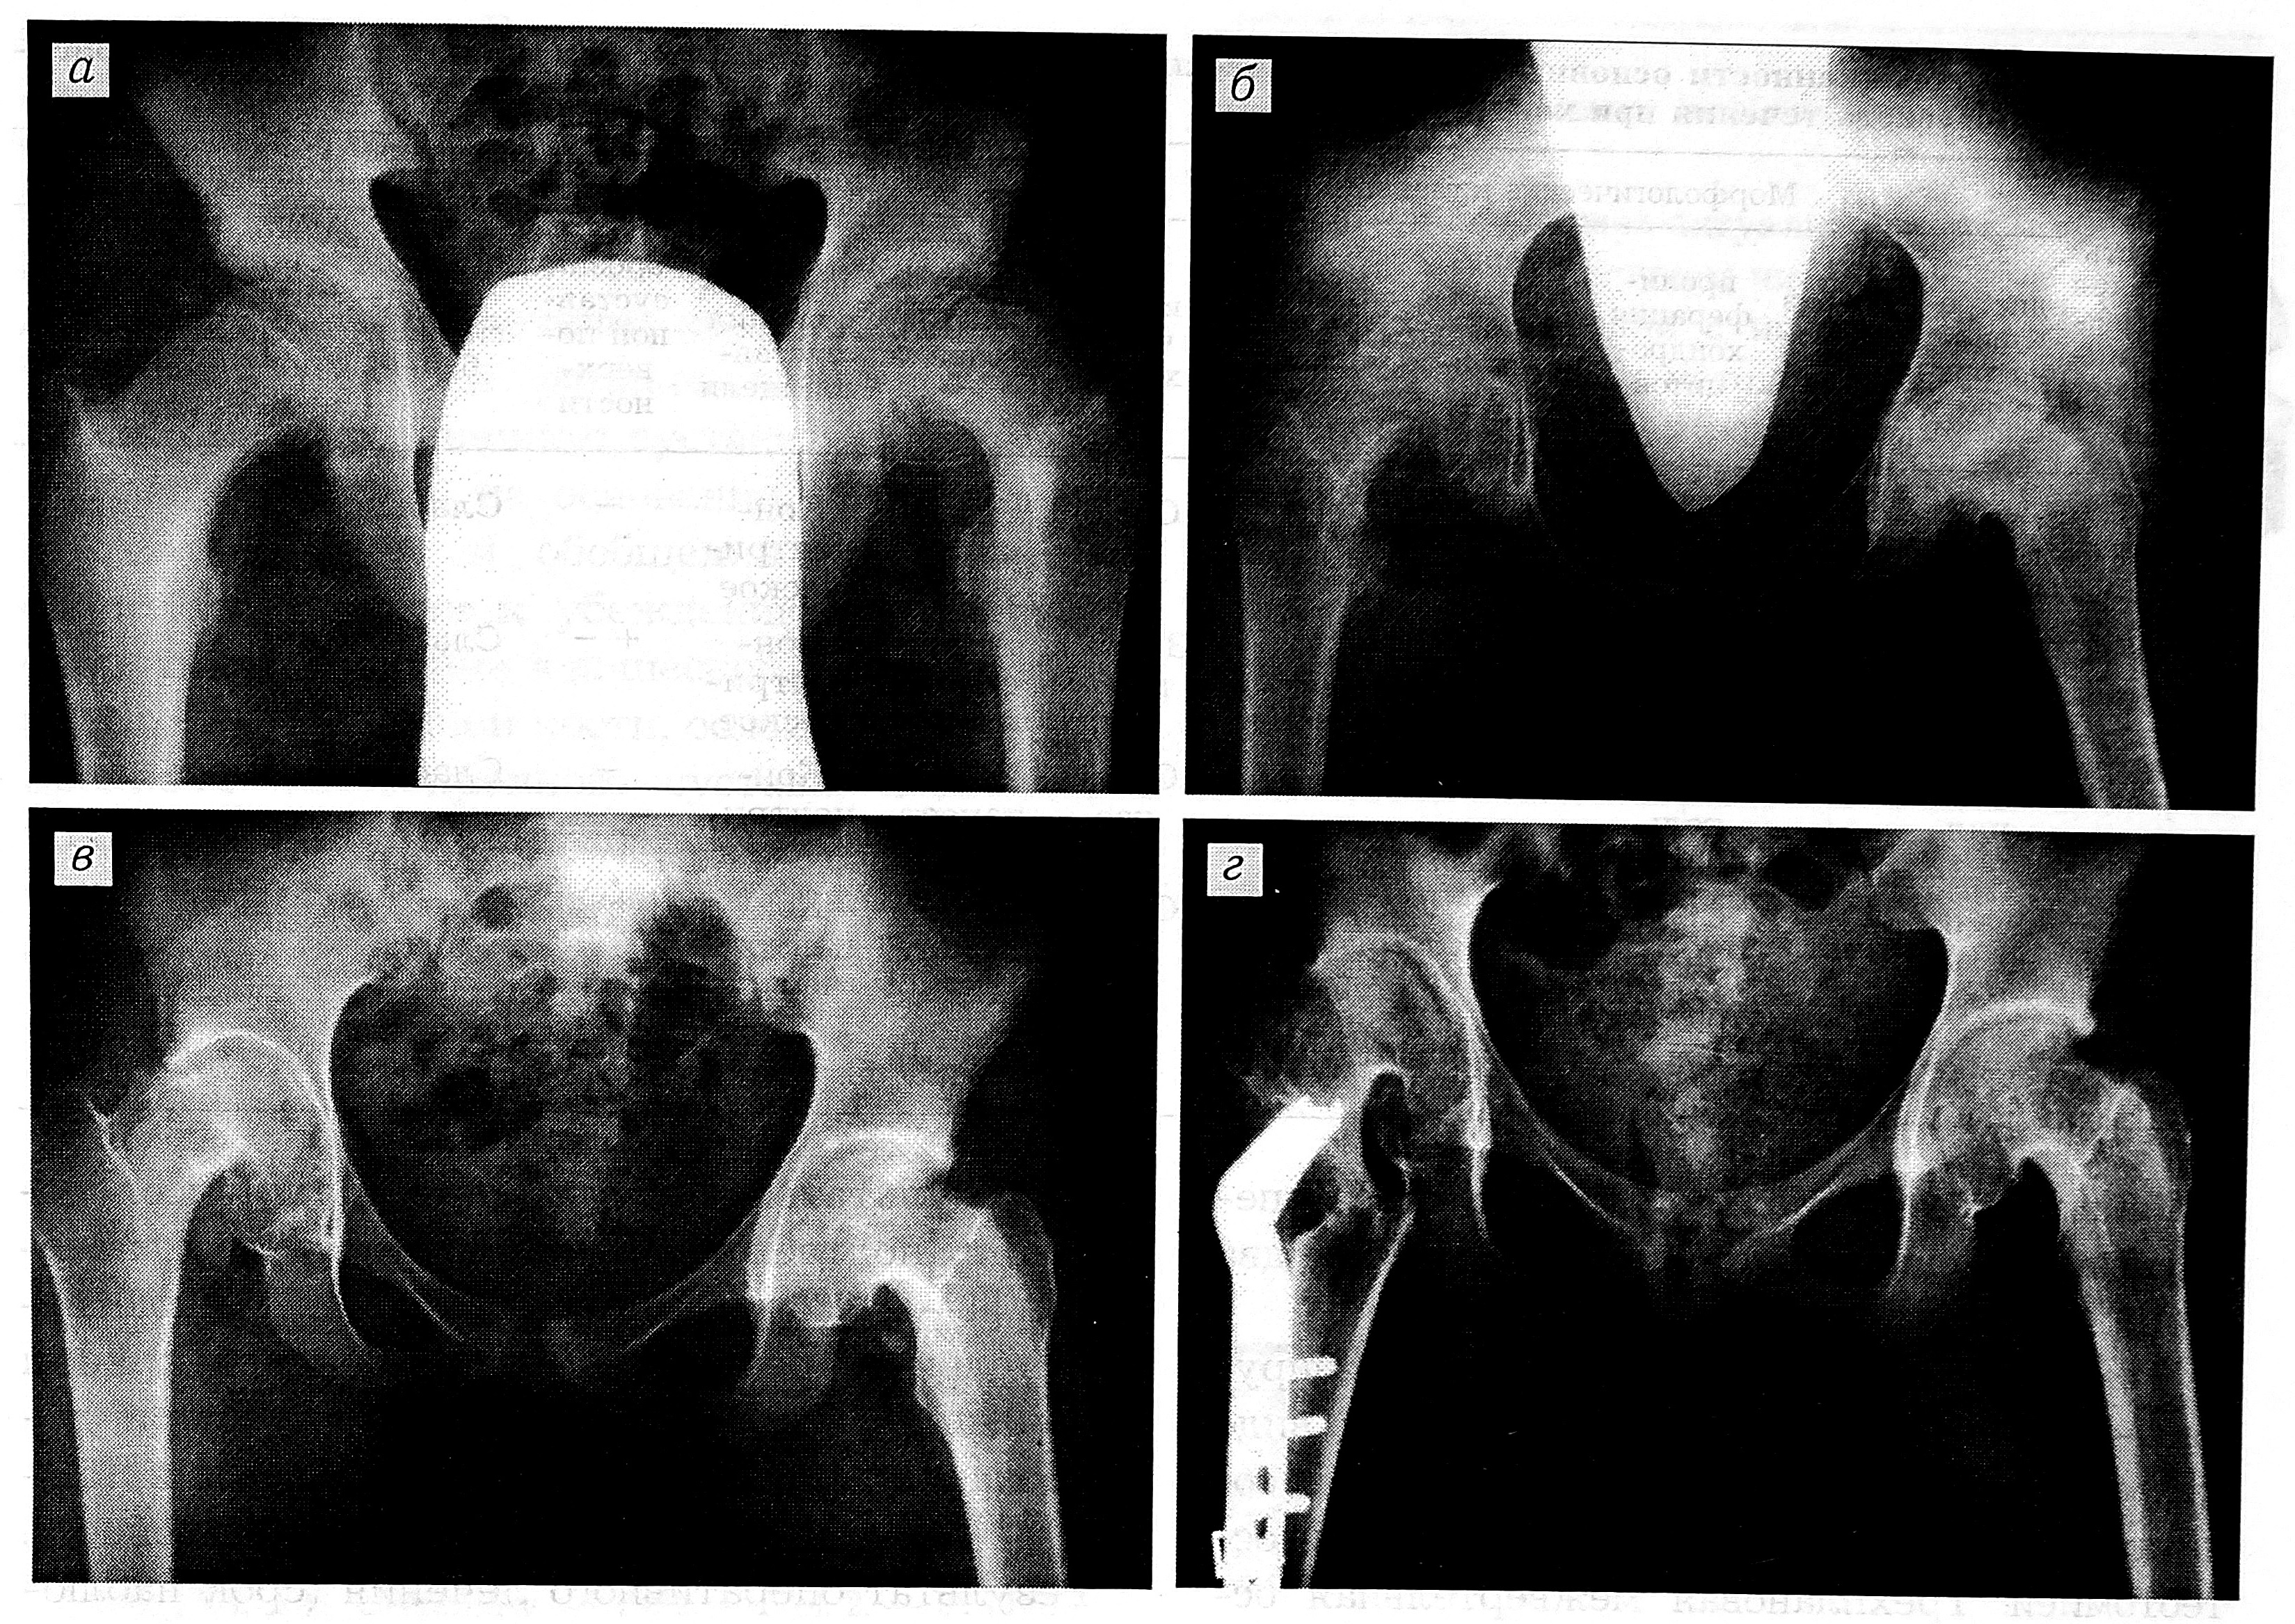

Теории возникновения хондролиза тазобедренного сустава разноречивы, но в вопросе о факторах, провоцирующих его, мнение большинства авторов едино [1—4, 6, 8, 9]: это закрытая репозиция смещенного эпифиза, гипсовая иммобилизация, скелетное вытяжение (результаты лечения скелетным вытяжением представлены на рисунке, а, б), интра- и послеоперационная пенетрация в сустав фиксаторов при выполнении эпифизеодеза, вальгизи-рующая остеотомия, хронический эпифизео-лиз со значительной степенью смещения.

Рентгенограммы больной Т., 15 лет, на этапах лечения. а — в момент установления диагноза: двусторонний юношеский эпифизеолиз головок бедренных костей; б — после лечения скелетным вытяжением (значительное сужение суставной щели, юкстаартикулярный остеопороз с обеих сторон; клинический диагноз: двусторонний хондролиз тазобедренных суставов); в — через 7 мес после одномоментно произведенных мобилизирующе-декомпрессивных операций (расширение суставных щелей); г — через 4 мес после межвертельной остеотомии по Imhouser— Southwick справа.

При осложненном юношеском эпифизеолизе головки бедренной кости основная цель — достичь движения в тазобедренном суставе путем мобилизирующей операции, что позволило бы осуществить посредством внесуставной остеотомии коррекцию положения смещенного эпифиза. В случае значительного остеопороза из-за невозможности применения стабильно-функционального остеосинтеза оперативное вмешательство производится в два этапа (см. рисунок, в, г).